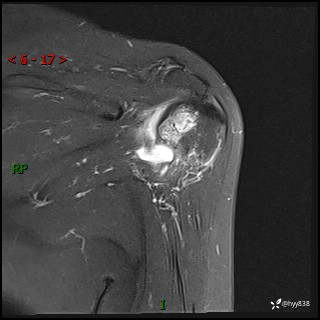

肱骨正侧位片

肱骨MRI平扫(axi T1WI+cor T2WI-fs)+CE-fs(COR+SAG)